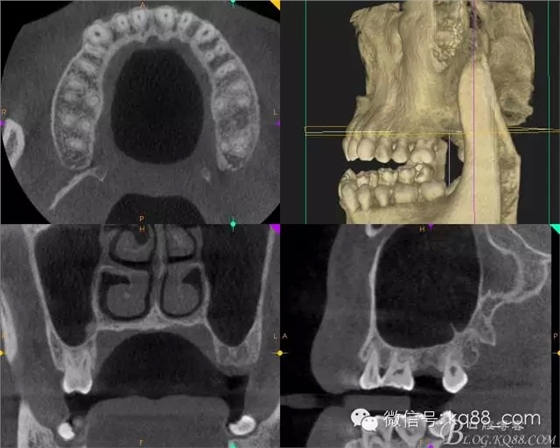

術(shù)前拍攝CT發(fā)現(xiàn)該處牙槽骨高度不足需要進(jìn)行內(nèi)提升手術(shù),但是 CT上看骨的寬度很好,所以決定采用微創(chuàng)植入。

術(shù)前的CT影像